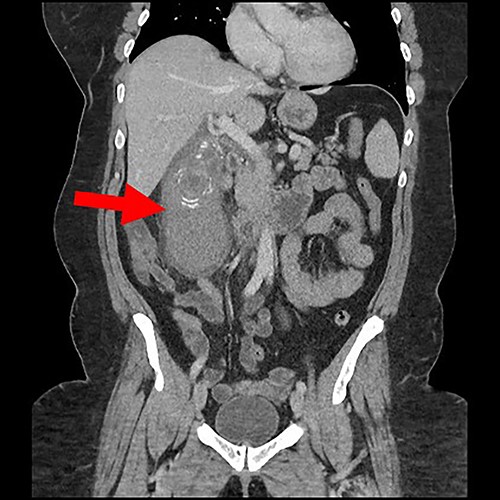

CT abdomen with intravenous contrast revealed a distended gall bladder containing numerous lamellate calculi and high-density fluid along with gall bladder wall thickness and pericholecystic fluid compatible with acute haemorrhagic calculus cholecystitis (see Figs 1 and 2).

Coronal view of gall bladder with high-density fluid and calculi.